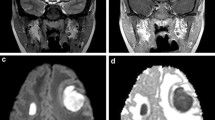

Patterns of cerebral edema in Parechovirus encephalitis and cerebral malaria. Axial DWI T2 (A–D), ADC maps (A′–D′). Case 1: a 10-day-old term baby admitted with fever, irritability and seizures. Diffusion (A, B) and ADC maps (A′, B′) in this case of Parechovirus encephalitis show radiating stripes of diffusion restriction in the periventricular and deep white matter with frontal predominance (arrows) and few smaller foci in the occipito-temporal regions. Diffusion restriction is also noted in the genu and splenium of corpus callosum (dashed arrows). Case 2: a 10-year-old boy with high-grade fever, comatose, and recent travel history. Diffusion (C, D) and ADC maps (C′, D′) in this case of cerebral malaria show subcortical predominant restricted diffusion in the frontoparietal regions bilaterally (arrows C, C′). Diffusion restriction in the splenium is noted as well, likely from excitotoxic intramyelinic edema (arrows, D, D′)

Cerebral malaria also provides an interesting avenue to study brain edema patterns. Imaging findings are on a spectrum and there are differences between children and adults [33]. The basal ganglia, thalami, white matter and cortex are commonly involved regions [34]. On diffusion weighted imaging (DWI), transient bilateral subcortical white matter restricted diffusion sparing the cortex is a common and characteristic finding in children (Fig. 4) [35]. This can be seen with or without callosal involvement and is associated with better outcomes and good neurological recovery [35]. This pattern is uncommon in adults who instead display a vulnerability of the basal ganglia and thalami [33, 35, 36].